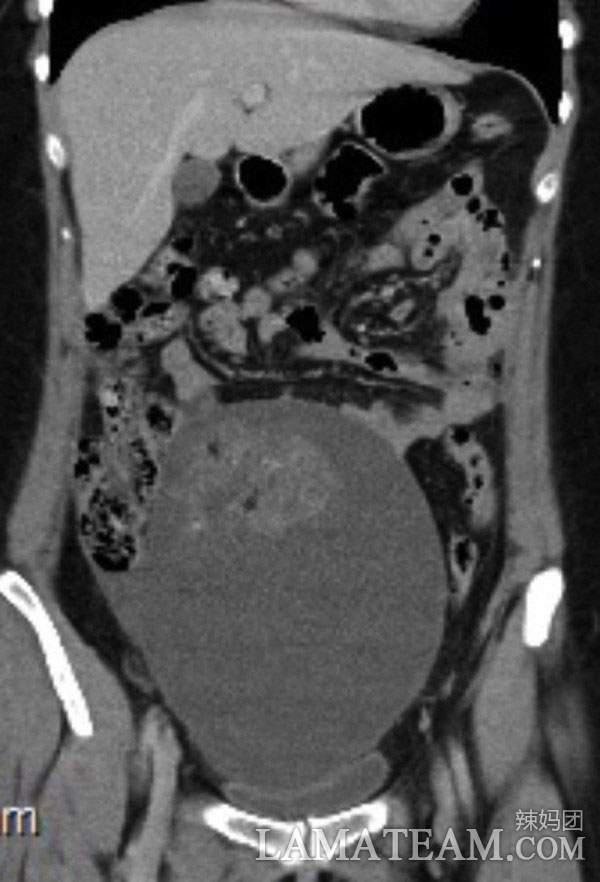

最後醫生做了活組織切片,結果表明路易斯患了未成熟卵巢畸胎瘤。

從片子中可以清楚地看到這個腫瘤已經佔據了她的整個胃部,還在壓迫著其他器官。這種情況只能手術,醫生先把腫瘤壓縮,到了可以移除的大小進行切除,然後修復卵巢和輸卵管,就這樣進行了4個小時的手術一切順利,而且還不會影響路易斯以後的生育。